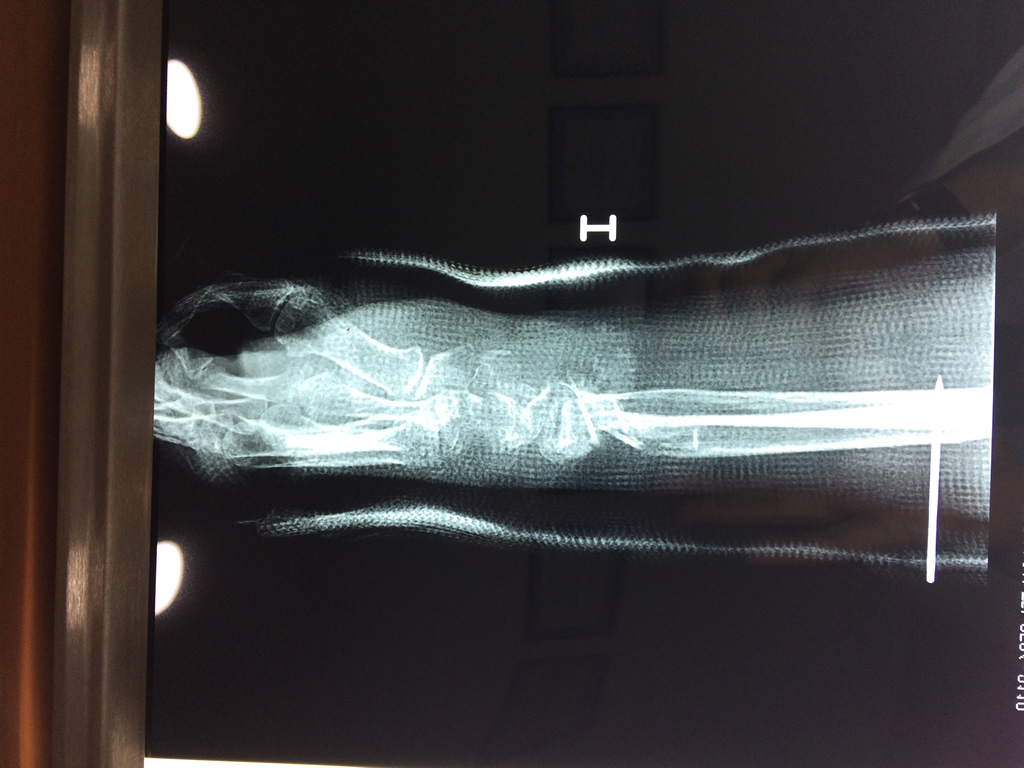

Cirugías de Codo - Cirugías de Muñecas y Manos

Los procedimientos más comunes en cirugía de la mano son aquellos destinados a reparar traumatismos, incluyendo lesiones de tendones, nervios, vasos sanguíneos, y articulaciones; huesos fracturados; y quemaduras, cortes, y otros daños de la piel.